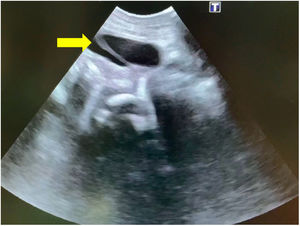

Under ultrasound guidance, the puncture was performed in the hypogastrium with a 16G angiocatheter (Fig. 1). The needle was removed and a 0.018-inch guide wire passed through the lumen to the bladder. A 3 Ch, 12cm long double-J stent was then passed over the wire and through the angiocatheter (Sof-Flex® Multi-Length Stent Set; Cook Medical, Bloomington, IN, USA), with verification of its correct placement by ultrasound (Figs. 2–3). The stent was fixed with 5-0 polypropylene monofilament and set to drain into an ostomy bag.